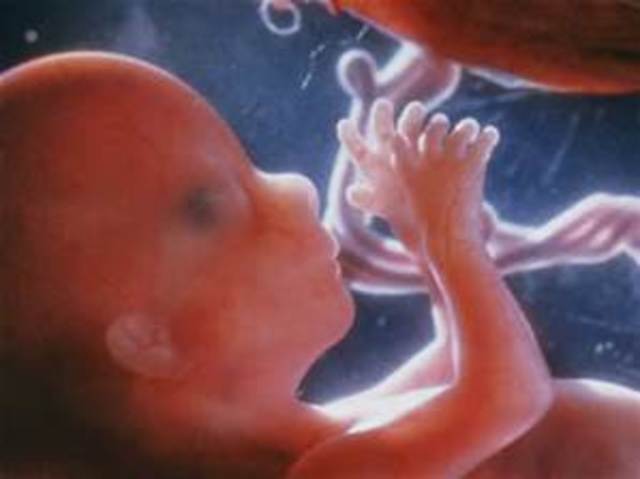

In week nine, the fingers and toes of the baby begin to develop; and it can now flex its elbows and wrists. Also during this week, the baby's head may appear larger than it's body due to the rapid growth of it's brain.

In week ten, the baby becomes a fetus and all of its organs, nerves, and muscles begin to function within its body. During this week of development the fetus is about the size of a strawberry.,